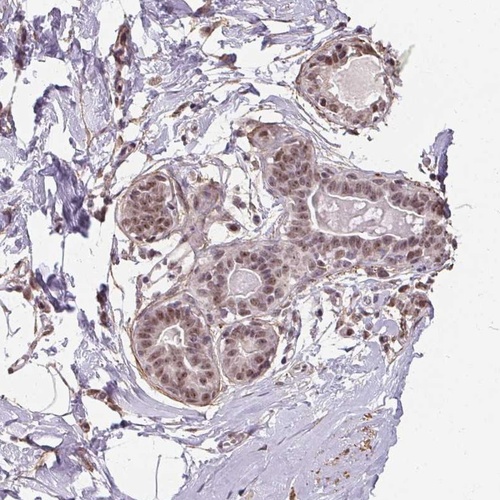

Immunohistochemical staining of human breast shows moderate nuclear positivity in glandular cells.